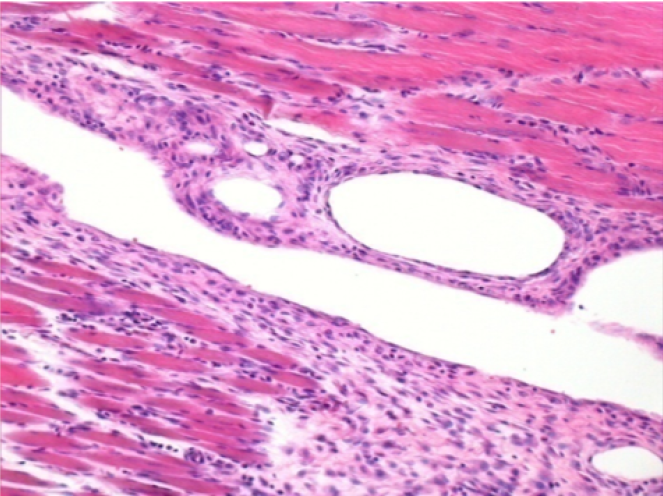

3 meses después de la inyección de Endopeel

3 meses (D90) después de la inyección de Endopeel 0.1ml en el músculo pretibial derecho.

L : Control-100xD90

R:100xD90